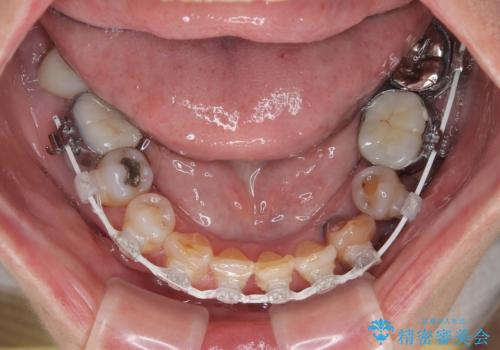

矯正治療に抵抗があったそうですが、前歯が欠けたことをきっかけに、矯正治療で歯列を整えた上で、セラミッククラウン治療を行う決心が付いたとのことでした。

デコボコが強いため、ブリッジや残根となっている部分のスペースを利用して歯列を整え、変色や欠けている歯をオールセラミッククラウンによる補綴治療を行うこととしました。

- 治療中は違和感や痛みが起こることがあります

- 症状により、抜歯が必要な場合があります

- 治療中は歯磨きがしにくくなるため、虫歯や歯周病になりやすくなります